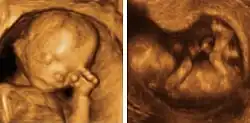

Ecografía fetal

Se utiliza para producir imágenes del feto mientras está en el útero para evaluar el crecimiento y desarrollo del bebé, y monitorear el embarazo. Por medio de esta prueba se pueden identificar muchas condiciones que pueden ser peligrosas tanto para la madre como para el hijo. Se utiliza para:[18]

- confirmar el embarazo y la ubicación (algunos fetos se desarrollan fuera del útero)

- determinar la edad de gestación del bebé

- confirmar la cantidad de bebés

- evaluar el crecimiento del bebé

- estudiar la placenta y los niveles de líquido amniótico

- identificar defectos congénitos

- investigar complicaciones

- realizar otros estudios prenatales

- determinar la posición del feto antes del parto.

Ecografía 3D y 4D

En los últimos tiempos se ha podido ver una revolución en el campo de la medicina materno-fetal. Esa revolución, además, no solo ha afectado a la medicina en sí misma, sino que ha aportado a la sociedad la posibilidad de establecer una unión emocional con los neonatos mucho más profunda de lo que hasta ahora se creía posible, gracias a una calidad de imagen que permite ver el aspecto del futuro bebé en fotografía (3D) o en imagen en movimiento (4D).

Para lograrlo, mediante el ecógrafo, se emiten los ultrasonidos en cuatro ángulos y direcciones, pasando el emisor suavemente por la barriga del paciente, a la cual se le ha aplicado previamente un gel para mejorar la eficiencia del proceso. Los ultrasonidos rebotan y son captados por el ordenador, que procesa automáticamente la información para reproducir en la pantalla la imagen a tiempo real del bebé.